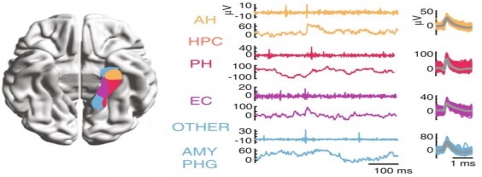

In addition to the very valuable iEEG recordings from the clinical macroelectrodes, our iEEG recordings also include signals recorded with microelectrodes. The additional microelectrodes have a diameter of about 40 μm (smaller than the hair) and spread out of the tip of the clinical intracranial electrode. They are added solely for research purposes and, because of their small size, they can record the electrophysiological firing activity generated by nearby individual neurons. We analyze this data by using algorithms which classify the different waveforms recorded by a single microwire into action potentials generated by different neurons. We also use population decoding methods to extract the information associated by the neurons (e.g. “concept” neurons which preferably fire in response to specific images of the same individual). To localize the site of the macro- and micro-electrodes with high spatial resolution, we combine post-implantation CT scans with pre-implantation neuroimaging scans from the 7-Tesla MRI, available at the University of Magdeburg.

| image credits [3] | image credits [5] | |

5. © Umbach et al., 2022. Reproduced according to the terms of Creative Commons Attribution License. Umbach, Gray, Ryan Tan, Joshua Jacobs, Brad E. Pfeiffer, and Bradley Lega. 2022. “Flexibility of Functional Neuronal Assemblies Supports Human Memory.” Nature Communications 13 (1): 6162. https://doi.org/10.1038/s41467-022-33587-0.